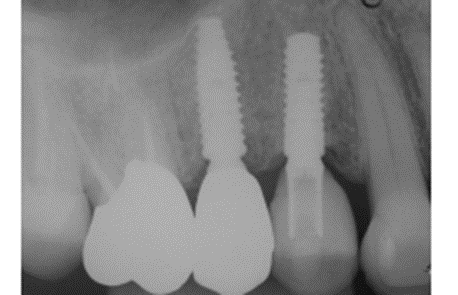

Foi eleito um implante Veloce Cone Morse de 3.75 X 11.5 mm e após a exodontia, o implante foi instalado utilizando o protocolo de fresagem recomendado pelo fabricante, fazendo uso das fresas escalonadas do sistema, alcançando um torque de inserção de 70 Ncm, o que me incentivou a promover o carregamento imediato deste implante (Figuras 5, 6, 7, 8, 9 e 10).

Diante das circunstâncias, foi eleito um pilar Ideale reto de 3.3 X 4.0 X 1.5 mm de transmucoso, que foi instalado a 20 Ncm. O escaneamento desse pilar foi realizado para a confecção de um provisório fresado em PMMA. Após 15 minutos da instalação e do escaneamento do pilar, o provisório fresado foi instalado sobre o pilar Ideale e aparafusado com o parafuso Torx a 10 Ncm. Foi então realizada uma radiografia após a instalação e a paciente foi marcada para retornos de 7 e 15 dias, sendo que após os retornos, a paciente realizou sua viagem (Figuras 11, 12, 13 e 14).

Na consulta seguinte a coroa final foi instalada e aparafusada com o parafuso Torx, e o orifício foi restaurado com resina fotopolimerizável. Foi realizada uma radiografia final e a paciente foi remarcada para retornar em seis meses para consulta de controle.